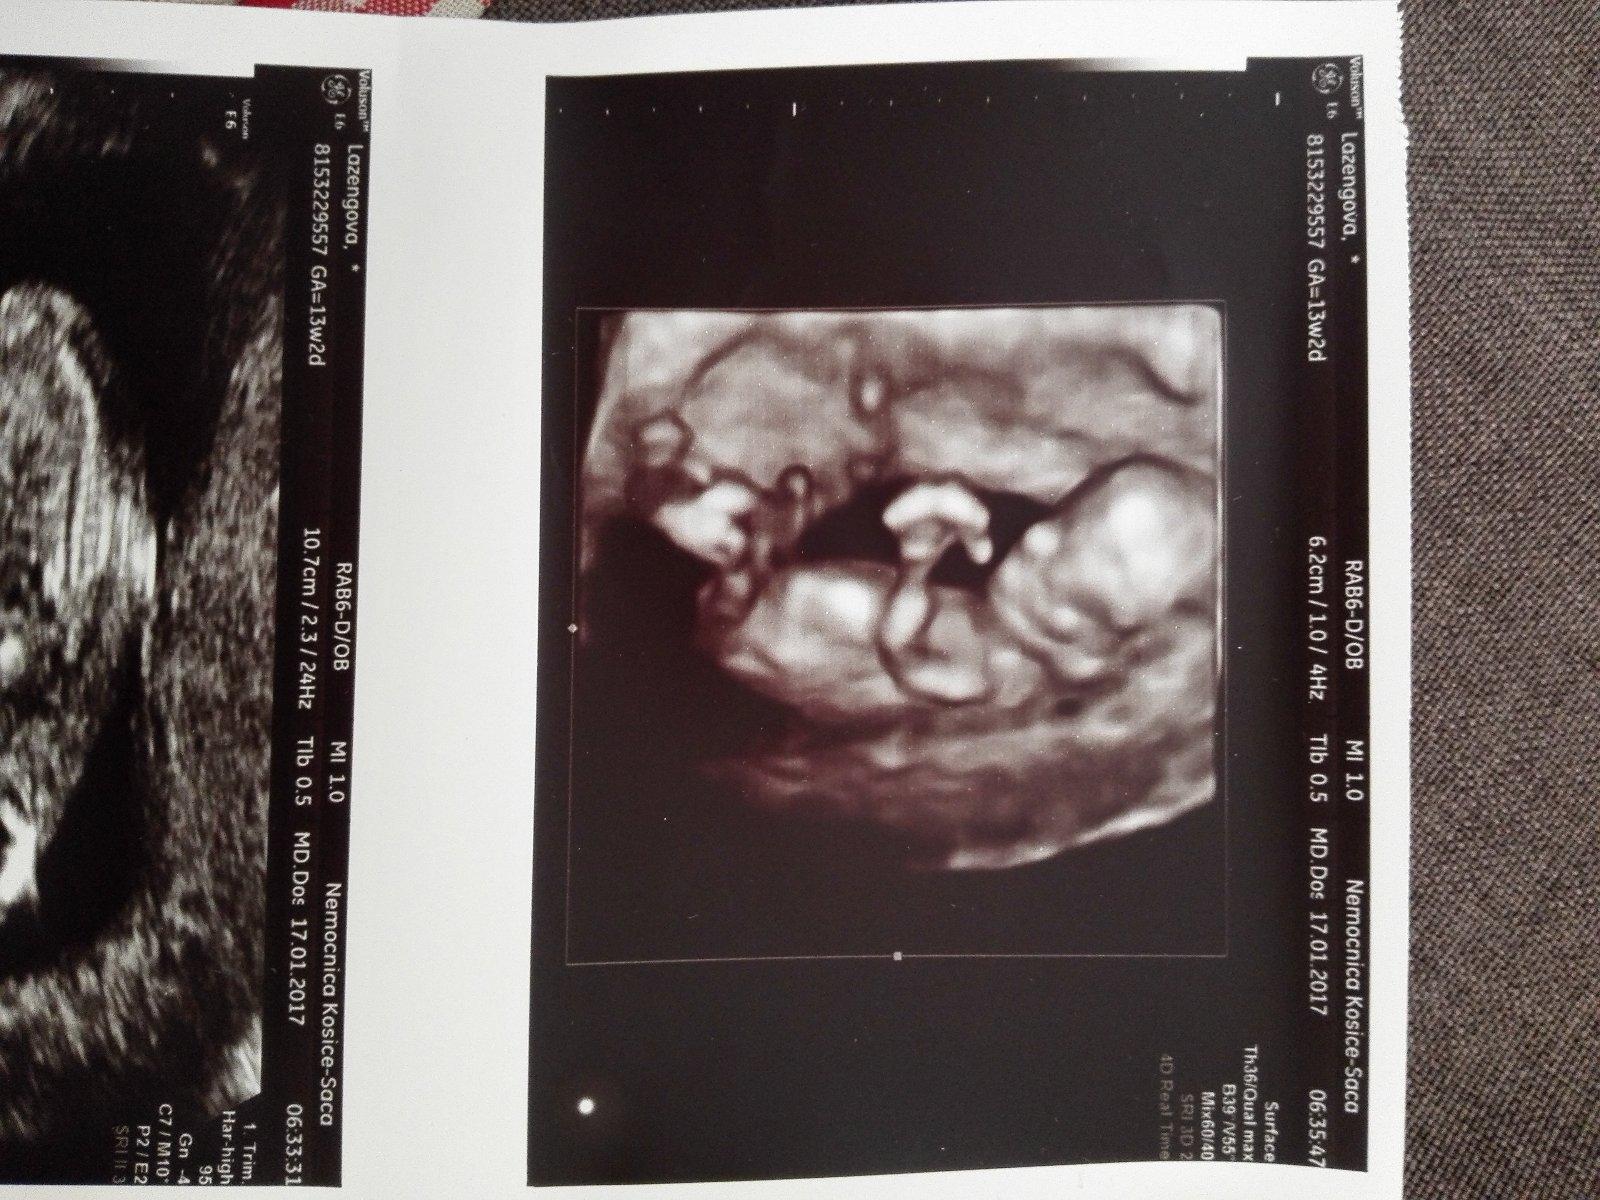

Ajojte,tak vcera sme absolvovali morfologivky usg a sa zmenil datum porodu na 30.7 a vyzera to tak ze budeme mat dievcatko 😍 ,sme od zaciatku mysleli ze bude chlapcek🙂 a zasli sme do lidla na nakup a som neodolala a som kupila body😎,dr.vylucil vyvojove vady,ale kvoli mojmu veku odporucil konzultaciu na genetike,ale bolo to nadherne ju vidiet,ako si tam plavala a ako menila polohu😍